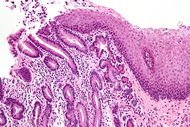

Micrograph of a gastro-esophageal junction with pancreatic acinar metaplasia. The esophageal mucosa (stratified squamous epithelium) is seen on the right. The gastric mucosa (simple columnar epithelium) is seen on the left. The metaplastic epithelial is at the junction (center of image) and has an intensely eosinophilic (bright pink) cytoplasm. H&E stain.

الحوؤل ( Metaplasia ) هو استبدال خلايا متمايزة ((differentiated cells من نوع معين بخلايا متمابزة من نوع آخر. الحوؤل مختلف عن خلل التنسج (dysplasia ) كما انه مختلف عن السرطان .

يؤدي الحوؤل إلى تغيير مآل الخلايا في مطلع حياتها ولا يغير الخلايا المتمايزة (differentiated cells).

الحوؤل عكوس (reversible ) وينجم عادة كاستجابة لالتهاب وتخريش مزمن ، ويتيح استبدال الخلايا باخرى اقدر على العيش في ظروف لاتحتملها الخلية الاصلية. و الحوؤل ليس ضارا في حد ذاته ولكنه يمكن أن يؤثر على بطانة اعضاء مختلفة كالقصبات (الطرق الهوائية) والمثانه. فالحوؤل في عنق الرحم يحدث تآكلا يمكن الكشف عنه باختبار لطاخة عنق الرحم.

الأهمية الطبية للحوؤل هي أن الخلايا قد تتطور من حوؤل إلى خلل تنسج ومن ثم إلى سرطان. و يحدث ذلك في مواقع عديدة من الجسم كالمثانه وعنق الرحم واسفل المريء. وعندما يكتشف الحوؤل في هذه المواقع ، نسعى سعيا جادا لازالة العوامل المسببة ، وبذلك نقلل من خطر ترقي الحوؤل إلى آفة خبيثة . ينبغي متابعة الناحية المصابة بالحؤول متابعة دقيقة لضمان كشف بدايات اي خلل تنسج الذي ان تطورت في العضو تطورا ملحوظا يستطب حينها ازالة المنطقة المصابة لمنع تطورها إلى سرطان.